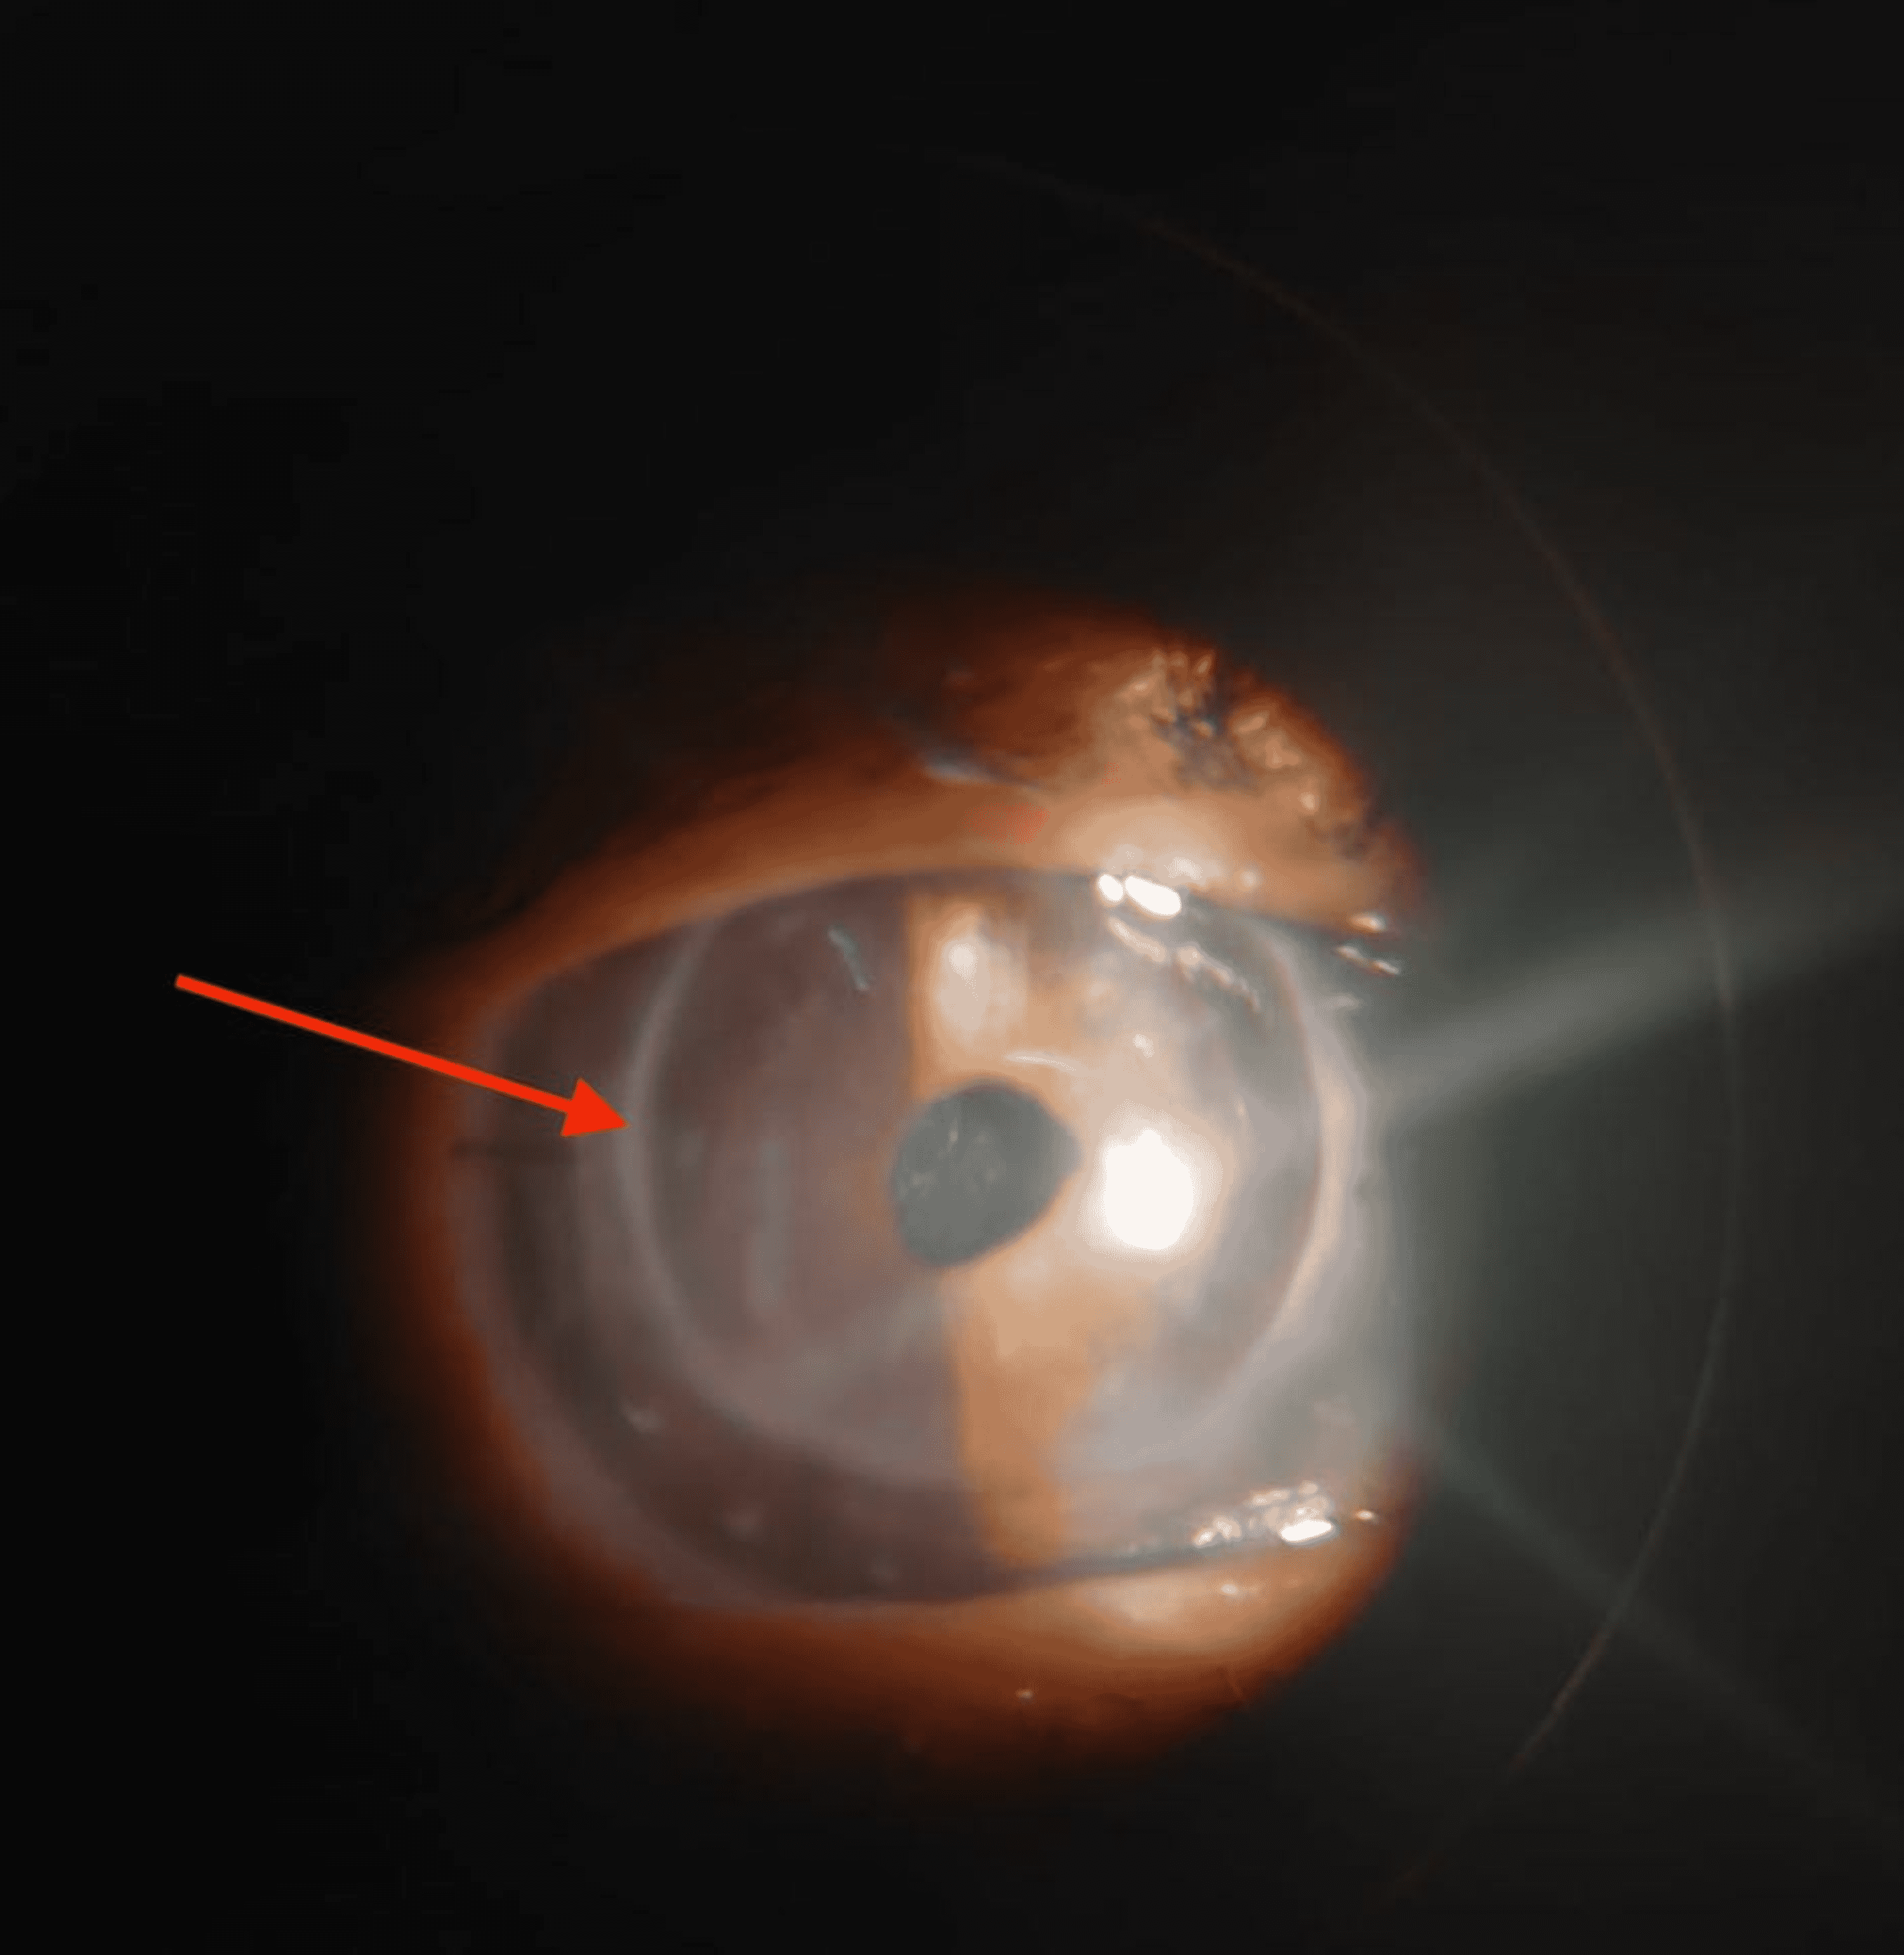

Cureus Complete Occlusion of Anterior Capsular Opening in Patient Operated for Cataract With

Cureus Complete Occlusion of Anterior Capsular Opening in Patient Operated for Cataract With Clouding Of Lens Capsule After Cataract Surgery Cloudiness in the eye after cataract surgery is a common complication called posterior capsule opacity (pco) that can be treated with a laser procedure called yag. Pco occurs because cells remaining. Posterior capsulotomy is a procedure that uses a laser to open the cloudy lens capsule behind the artificial lens implanted. Posterior capsulotomy is a laser procedure to remove scar. Clouding Of Lens Capsule After Cataract Surgery.